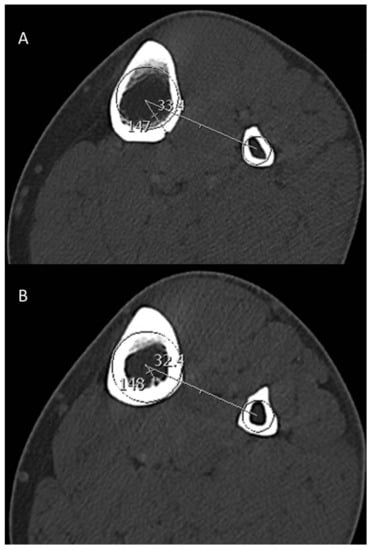

-Angular location of outer and inner foramina with respect to the circumference of the tibia using the fibula as the reference point (Figure 3).

Figure 3. Axial reformatted images in bone window indicating the angular position of the outer foramen of TNAC on the outer cortex (A) and the angular position of the inner foramen on the inner cortex (B). The angular position is defined by a line connecting the two centers of the tibia and fibula and an intersecting line connecting the center of the tibia to the respective foramen.

4. Discussion

A thorough understanding of the TNAC topography has crucial clinical relevance in the context of trauma surgery, reconstructive surgery, radiographic assessment and bone healing. The tibia is the most commonly fractured long bone in humans and consequently constitutes a huge burden on health-care costs [9,15,16,17,18]. Osseous regions with better vascular supply tend to heal faster than regions with lesser vascularity [15]. In other words, tibial fractures in which the tibial nutrient artery is damaged tend to have an increased incidence of non-union or delayed union [15]. Additionally, iatrogenic damage to the tibial nutrient artery may occur during positioning of internal and external fixation devices hampering fracture healing later on. “Safe corridors” for pin and wire placement have been established, within which iatrogenic injury to nerves and vessels is less likely to occur [19]. However, those classic “safe corridors” of pin placement have been defined to avoid injury to the major neurovascular structures in the lower extremity without considering the TNAC [4,19,20,21]. The position of the pins should classically maintain the stability of the fractured tibia by counteracting the forces which are exerted on the leg (anteroposterior and transverse bending moments) [19,22]. The anteromedial position is usually recommended for pin placement “either in a sagittal plane medial to the tibial crest or perpendicular to the anteromedial surface of the tibia” [21]. The AO Surgery Reference Manual (AO stands for “Arbeitsgemeinschaft für Osteosynthesefragen” and is a world renowned nonprofit organization dedicated to improving the care of people with musculoskeletal injuries) describes a safe corridor with a trajectory angle “(relative to the sagittal plane) of 20–60° for the proximal fragment” [20]. Our study shows that the TNAC mostly traverses in the middle third of the postero-lateral tibia at mean angular location of the inner and outer foramen between 20–30° (Table 2) (Figure 3). Hence, surgeons should exercise caution while inserting pins at the proximal tibia despite the officially recommended “safe corridor”.